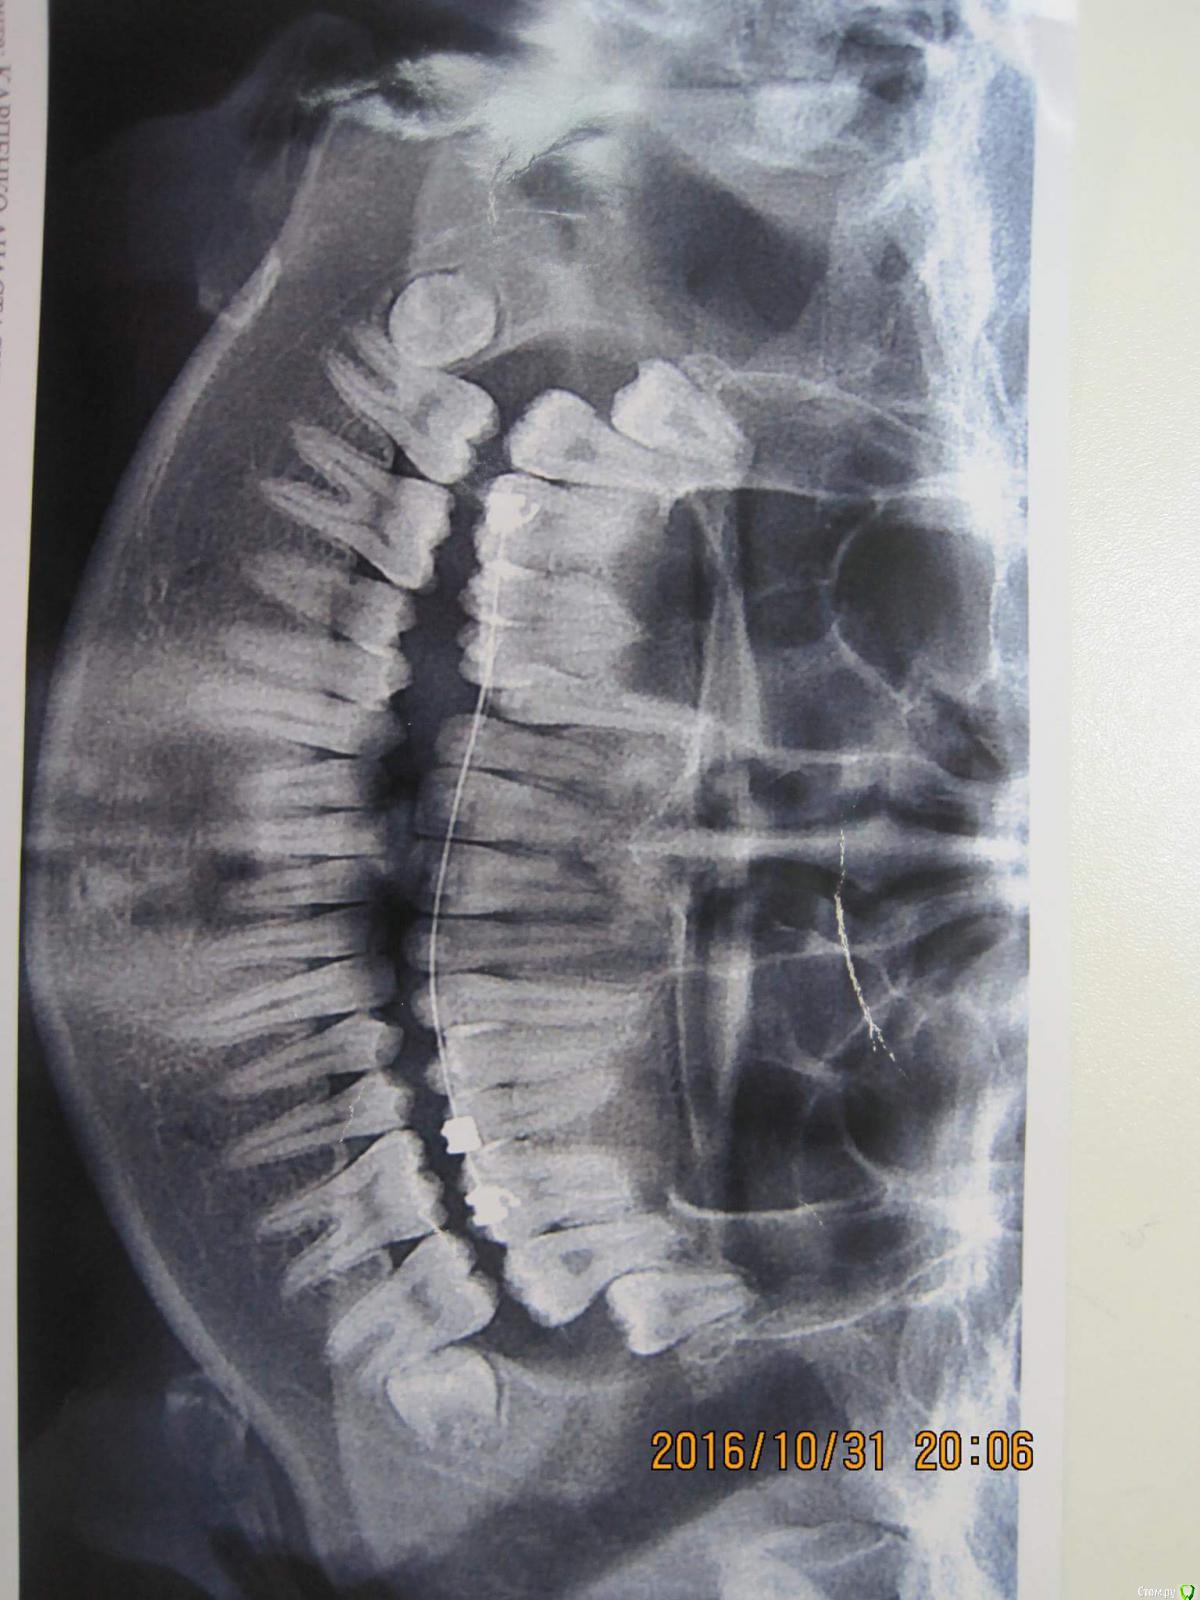

simpsons Опубликовано 8 декабря, 2016 Поделиться Опубликовано 8 декабря, 2016 Пытаемся вытянуть 13, но попытки тщетны... хочу знать мнения как поступают в таких ситуациях , если есть заместительная резорбция корня ( анкилоз)? Ссылка на комментарий

Yana guapa Опубликовано 9 декабря, 2016 Поделиться Опубликовано 9 декабря, 2016 Пытаемся вытянуть 13, но попытки тщетны... хочу знать мнения как поступают в таких ситуациях , если есть заместительная резорбция корня ( анкилоз)? 1. во-первых, хотелось бы спросить откуда такой диагноз? (Заместительная резорбция Зубоальвеолярный анкилоз может проявляться образованием костной ткани в ответ на обширный некроз периодонтальной связки. Клинически это состояние обычно является осложнением подвывихов или вывихов зубов, а особенно полных вывихов, при которых зубы находились вне полости рта достаточно длительное время, в связи с чем произошла гибель клеток периодонтальной связки и нарушение прикрепления в области корня. Если в процесс вовлекается менее 20% поверхности корня, явления анкилоза оказываются обратимыми.В противном случае зуб становится частью альвеолярной кости и включается в процесс нормальной перестройки костной ткани. Соответственно, происходит постепенная резорбция тканей зуба и замещение их костной тканью, в связи с чем процесс называют заместительной резорбцией. Остеокласты, являющиеся основными клетками, участвующими в процессе заместительной резорбции, осуществляют ремоделировку костной ткани. Клинически зубоальвеолярный анкилоз характеризуется исчезновением подвижности зуба. При перкуссии определяется специфический металлический звук, а со временем зубы оказываются в инфраокклюзии. Рентгенологически наблюдается исчезновение периодонтальной щели. Кроме того, врастание кости в ткани зуба в процессе заместительной резорбции придает зубу характерный «изъеденный» вид.) это я так, для себя. Мы об одном и том же думаем? 2. или Вы решили , что зуб анкилозирован, только из-за того, что не выходит? Я могу предположить, что у зуба есть шанс, если все сделать грамотно. - создать место-использовать удобные и быстрые дуги (типа cantilever или ballista ) 3. конечно такие кейсы нужно оформлять более информативно, если хотите получить больше советов ( фото прикуса в фас, профиль; лицо), срезы КТ http://i12.pixs.ru/thumbs/4/4/8/IMG4417JPG_3567295_24358448.jpg http://i12.pixs.ru/thumbs/4/6/0/IMG4426JPG_9513930_24358460.jpg 1 Ссылка на комментарий

Yana guapa Опубликовано 9 декабря, 2016 Поделиться Опубликовано 9 декабря, 2016 Пытаемся вытянуть 13, но попытки тщетны... хочу знать мнения как поступают в таких ситуациях , если есть заместительная резорбция корня ( анкилоз)? что со средний линией? походу именно с ней и нужно работать. Брекеты на 7ках не стоят.... Опору терять начинаете... надо ставить нормальную полноценную систему, развивать зубные арки, центровать средние линии, создавать место , тянуть и ..... конечно же молиться!)))))) 1 Ссылка на комментарий

simpsons Опубликовано 10 декабря, 2016 Автор Поделиться Опубликовано 10 декабря, 2016 1. во-первых, хотелось бы спросить откуда такой диагноз? (Заместительная резорбция Зубоальвеолярный анкилоз может проявляться образованием костной ткани в ответ на обширный некроз периодонтальной связки. Клинически это состояние обычно является осложнением подвывихов или вывихов зубов, а особенно полных вывихов, при которых зубы находились вне полости рта достаточно длительное время, в связи с чем произошла гибель клеток периодонтальной связки и нарушение прикрепления в области корня. Если в процесс вовлекается менее 20% поверхности корня, явления анкилоза оказываются обратимыми.В противном случае зуб становится частью альвеолярной кости и включается в процесс нормальной перестройки костной ткани. Соответственно, происходит постепенная резорбция тканей зуба и замещение их костной тканью, в связи с чем процесс называют заместительной резорбцией. Остеокласты, являющиеся основными клетками, участвующими в процессе заместительной резорбции, осуществляют ремоделировку костной ткани. Клинически зубоальвеолярный анкилоз характеризуется исчезновением подвижности зуба. При перкуссии определяется специфический металлический звук, а со временем зубы оказываются в инфраокклюзии. Рентгенологически наблюдается исчезновение периодонтальной щели. Кроме того, врастание кости в ткани зуба в процессе заместительной резорбции придает зубу характерный «изъеденный» вид.) это я так, для себя. Мы об одном и том же думаем? 2. или Вы решили , что зуб анкилозирован, только из-за того, что не выходит? Я могу предположить, что у зуба есть шанс, если все сделать грамотно. - создать место-использовать удобные и быстрые дуги (типа cantilever или ballista ) 3. конечно такие кейсы нужно оформлять более информативно, если хотите получить больше советов ( фото прикуса в фас, профиль; лицо), срезы КТ Спасибо. Об одном и том же. Ссылка на комментарий

simpsons Опубликовано 10 декабря, 2016 Автор Поделиться Опубликовано 10 декабря, 2016 что со средний линией? походу именно с ней и нужно работать. Брекеты на 7ках не стоят.... Опору терять начинаете... надо ставить нормальную полноценную систему, развивать зубные арки, центровать средние линии, создавать место , тянуть и ..... конечно же молиться!)))))) Центральная линия смещена. Спасибо!) Ссылка на комментарий